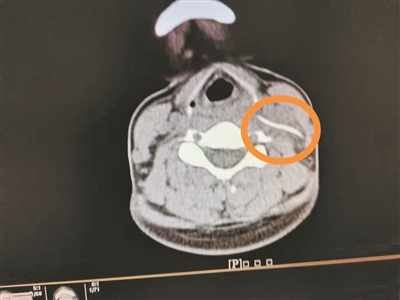

影像檢查顯示頸部異物。

4月1日,陳女士帶女兒到南方醫(yī)科大學(xué)第三附屬醫(yī)院就診,想起自己頸部不舒服,就順便到耳鼻咽喉科就診,副主任醫(yī)師曹慶碩接診后,請(qǐng)患者平躺檢查,此時(shí)陳女士感覺頸部更痛了,醫(yī)生懷疑頸部有異物,于是進(jìn)行了頸部CT平掃,果然發(fā)現(xiàn)左側(cè)頸動(dòng)脈鞘區(qū)有異物。

明確診斷后,醫(yī)生為陳女士安排4月2日手術(shù),行“頸部側(cè)切開異物取出術(shù)”,術(shù)中見一魚刺橫行于甲狀軟骨平面的咽旁間隙內(nèi),緊貼頸內(nèi)靜脈、頸總動(dòng)脈后方,周圍炎性組織包裹,幸好頸部血管無損傷,分離包裹的炎性組織,取出異物,長(zhǎng)3.3cm。